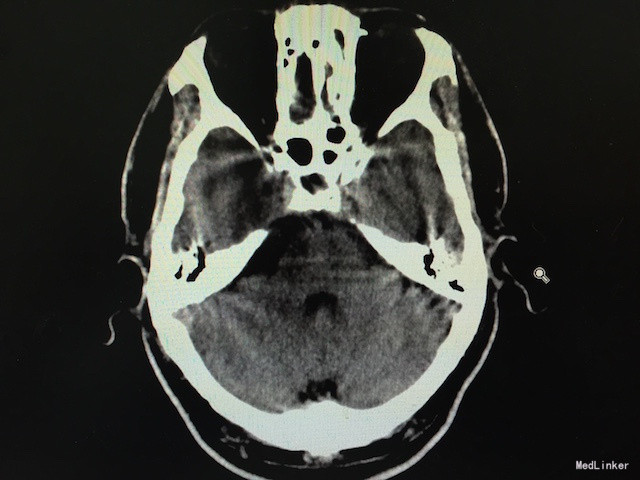

查体:右侧面部疼痛诱发有明显的扳机点,累及三叉神经1、2、3支;感觉无明显异常,四肢肌力、肌张力可;病理征(-)。 辅助检查:头颅CT未见桥脑角区明显占位。

随访及讨论:术程顺利,术后患者恢复出院,术后病理回报为胆脂瘤,无听力减退等术后颅神经损伤并发症。一般胆脂瘤压迫导致的三叉神经痛,CT平扫显示不明显,且症状并不典型,常规行头颅MRI不现实,故对于这类由于继发性因素引起的三叉神经痛,术中可以诊断及去除病因。